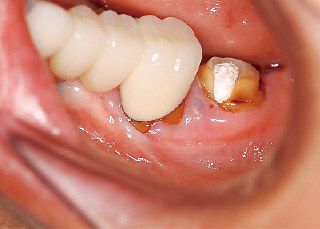

症例2:瘻孔の原因歯をデンタルから判定できなかった症例

46歳女性で、他院で下顎左側第二大臼歯の根管治療を開始したが、瘻孔が消えないために紹介で来院した。

瘻孔は患歯近心歯頸部に見られた(図4)。デンタルX線写真では患歯根尖に透過像が認められたが、瘻孔から挿入したガッタパーチャは近心根の途中で止まっていた(図5)。

図4 #37近心歯頸部の瘻孔。